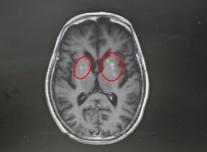

该院神经内一科副主任匡祖颖接诊后,详细询问病史并进行查体,结合影像检查结果,迅速锁定了病因——非酮症高血糖性偏侧舞蹈症。影像显示,王奶奶的双侧基底节区出现异常信号。进一步追问得知,她两年前查出高血糖,但一直没有规律服药,往往只在自我感觉血糖升高时才吃一点降糖药。这次入院后测出的空腹血糖高达13mmol/L,餐后血糖更达到21mmol/L,是正常值的两倍。匡祖颖解释,这种病多见于血糖控制不佳的人群,核心诱因正是长期严重的高血糖“烧坏”了大脑深部的纹状体。